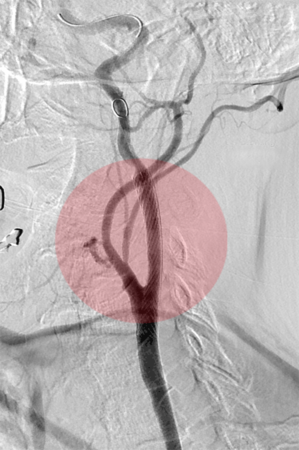

Therapeutische Verfahren - Interventionen

Zur Behandlung von Gefäßerkrankungen stehen uns neben Gefäßoperationen auch minimal invasive Therapiemethoden zur Verfügung. Hierzu gehören Eingriffe an Arterien oder Venen der Arme und Beine, des Halses sowie des Brust- und Bauchraumes. Diese werden über einen durch Punktion geschaffenen Gefäßzugang mit Hilfe spezieller Drähte, Katheter u. ä. durchgeführt. In der Regel sind diese Interventionen sehr schmerzarm.

Nachfolgend erhalten Sie einen Überblick der gängigen Methoden, die im Oberlausitzer Gefäßzentrum zur Anwendung kommen. Abhängig vom Schweregrad der Durchblutungsstörung erfolgt oft eine Kombination der verschiedenen Verfahren.

7. Embolisation – Verschluss von Gefäßen

Bei Blutungen durch Gefäßverletzungen, Gefäßmissbildungen, Tumorerkrankungen o. ä kann es sich in der Behandlung notwendig machen, Blutgefäße von innen zu verschließen. Dazu werden über Katheter am Ort des geplanten Gefäßverschlusses kleine Verschlusskörper, Verschlussspiralen oder verschließende Flüssigkeiten injiziert. Bei Tumoren ist auch die lokale Gabe von Chemotherapeutika möglich.